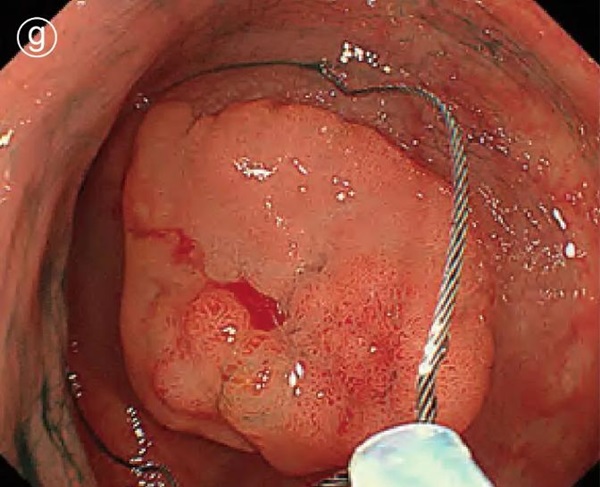

g. Open the snare

Press the snare tip against the colon wall to open the snare.